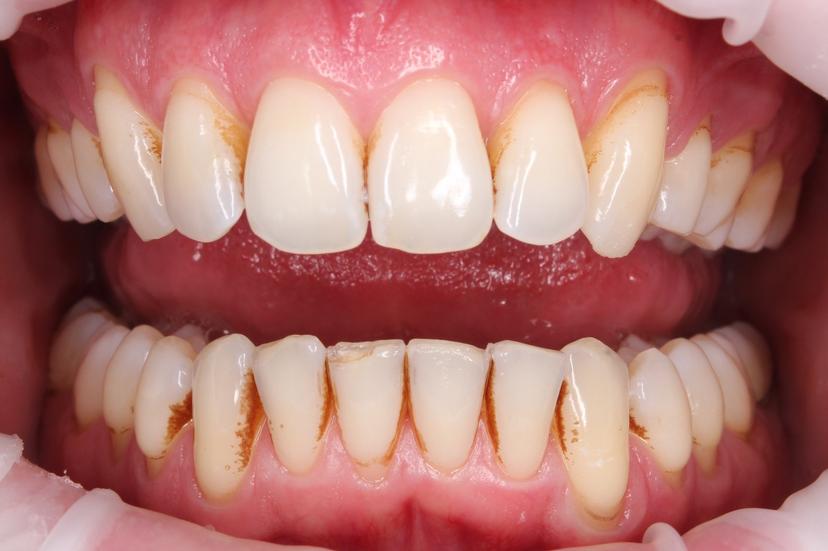

ДО: Заметны налет, пигментация и твердые зубные отложения, что придает неухоженный вид зубам.

После: Поверхность зубов очищена, восстановлен их естественный цвет, отсутствуют твердые зубные отложения и налет. Зубы выглядят здоровыми и ухоженными, а десны - свежими и более розовыми.